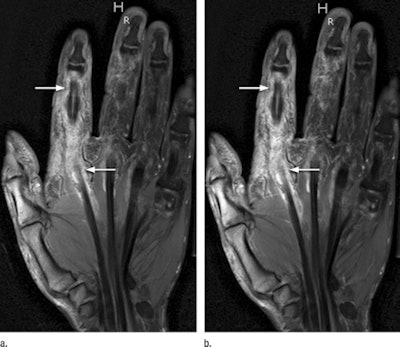

Gadobenate dimeglumine (MultiHance, Bracco) was measured in inflamed synovial tissue at half dose (0.05 mmol/kg of body weight) and at full dose (0.1 mmol/kg) using T1-weighted MRI sequences with fat saturation. Each contrast injection was followed by a 20-mL saline flush.

Two readers who were blinded to the patient data separately analyzed all images, with the half-dose and full-dose MR images mixed before evaluation. Their analysis included quantitative measurements of signal intensity in the inflamed synovial tissue, signal-to-noise ratio, and contrast-to-noise ratio.

Despite the disparity in contrast-to-noise and signal-to-noise ratios between the dosages, the diagnostic quality of the images was not affected, according to the authors. No region of synovial inflammation seen on full-dose contrast-enhanced MRI was missed at half dose.